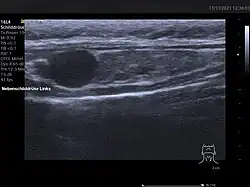

Vor einer geplanten Operation können Lokalisation und Größe der betroffenen Nebenschilddrüsenkörperchen durch Sonografie, Szintigrafie mit Technetium-99m-Sestamibi (Nebenschilddrüsenszintigrafie), Computertomographie oder Kernspintomografie dargestellt werden.

Ultraschallbild einer Schilddrüse vom Hund mit Adenom der Nebenschilddrüse

Die Sensitivität dieser diagnostischen Verfahren ist jedoch begrenzt. Besonders bei komplizierteren Fällen, wie zum Beispiel bei Vorhandensein von mehreren auffälligen Nebenschilddrüsen oder entfernt auftretenden Nebenschilddrüsenadenomen, kann eine zuverlässige Lokalisation aller betroffenen Epithelkörperchen schwierig sein.[60] Neuere bildgebende Verfahren, wie Positronenemissionstomographie (PET) mit speziellen Radiopharmaka wie 68Ga-Trivehexin, können in solchen Fällen eine zuverlässigere Lokalisation ermöglichen,[61] wodurch deren komplette chirurgische Entfernung und damit eine vollständige Heilung des primären Hyperparathyreoidismus wahrscheinlicher wird.